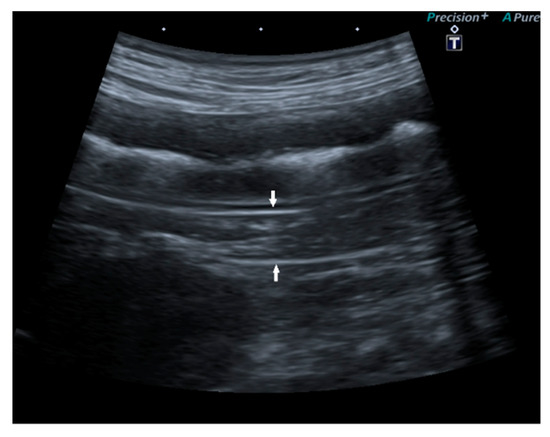

Pancreatic size was determined using calipers on a video frame or a still image. As described in the previous study, given that the pancreas has a triangular shape, it was considered a good compromise to measure its thickness perpendicular to the long axis [17]. Due to the low identification rate of the left pancreas in dogs, the pancreatic thickness was evaluated by measuring the right lobe located ventromedial to the right kidney and medial to the descending duodenum (Figure 1) [17].

Figure 1.

Ultrasound images (a) and (b) of the right pancreatic limb (between white arrows) with caliper measurement.